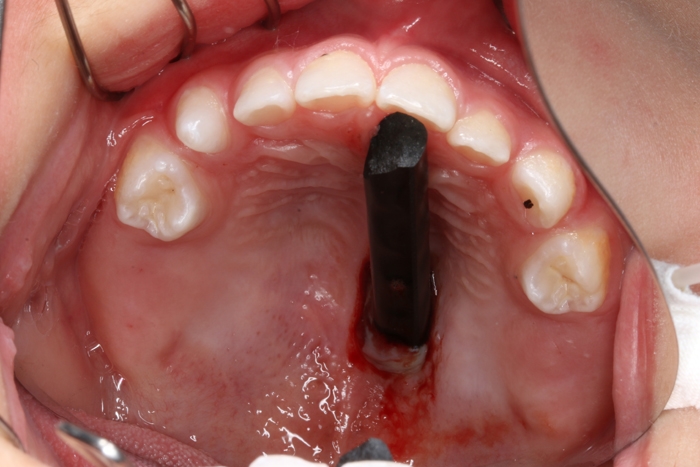

驚!半截筷子直插口腔上顎

??? 當日下午,楊先生家兩歲的兒子在家中拿著一根筷子蹦蹦跳跳,四處跑動,看到有燒熟的玉米就自己將玉米插在筷子上,邊玩耍邊吃。一不小心,孩子一個趔趄摔倒在地,當家人跑過去扶起他時,發(fā)現(xiàn)筷子斷成了兩截,其中一段插在了孩子的口腔里。孩子撕心裂肺的哭聲,插在寶寶口腔上顎的筷子讓他們一家人束手無策。在當?shù)蒯t(yī)院醫(yī)生的建議下,楊先生立刻將孩子送到了衢州市人民醫(yī)院就診。

??? 據(jù)接診的口腔科徐醫(yī)生介紹,患兒來院時筷子戳入口腔上顎的深度不明,貿(mào)然拔出可能有出血不止的風(fēng)險,因此立即安排患兒做了急診CT,在確定筷子位置和深度的情況后,急診為患兒行顎部裂傷清創(chuàng)縫合術(shù)。

術(shù)前